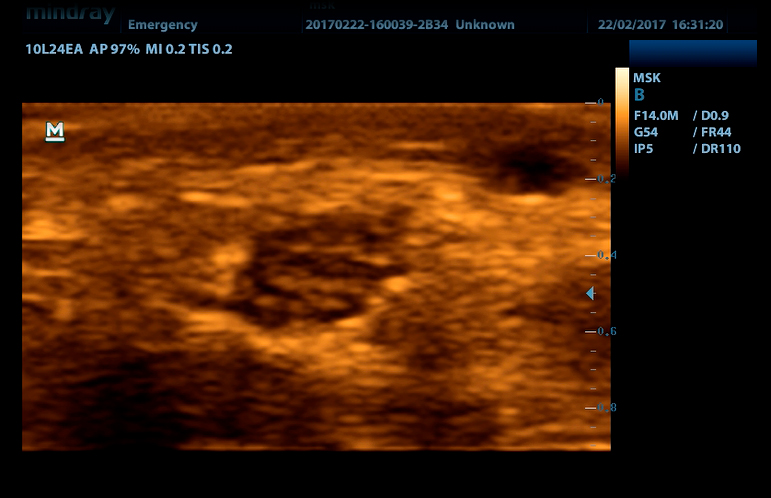

УЗ-сканер DP-50 Color представляет собой новое поколение ультразвуковых систем с цветных доплером компании Mindray. Он оснащен передовыми технологиями визуализации, обеспечивающими более глубокое проникновение и быстрое получение изображений при более высоком разрешении. УЗ-сканер DP-50 color отлично подходит для всех клинических ситуаций благодаря своей новой высокотехнологичной конструкции, повышенной мобильности и удобству эксплуатации.

- Широкий выбор мультичастотных датчиков от 2,0 до 14,0 МГц

iBeam Позволяет использовать несколько углов сканирования для формирования единого изображения, что приводит к увеличению контрастного разрешения и улучшению визуализации.

iClear Позволяет улучшить качество изображения, основываясь на автоматическом распознавании структур.

- Линейный датчик 75L38EA, 3.3 - 13.0 МГц, апертура 38 мм